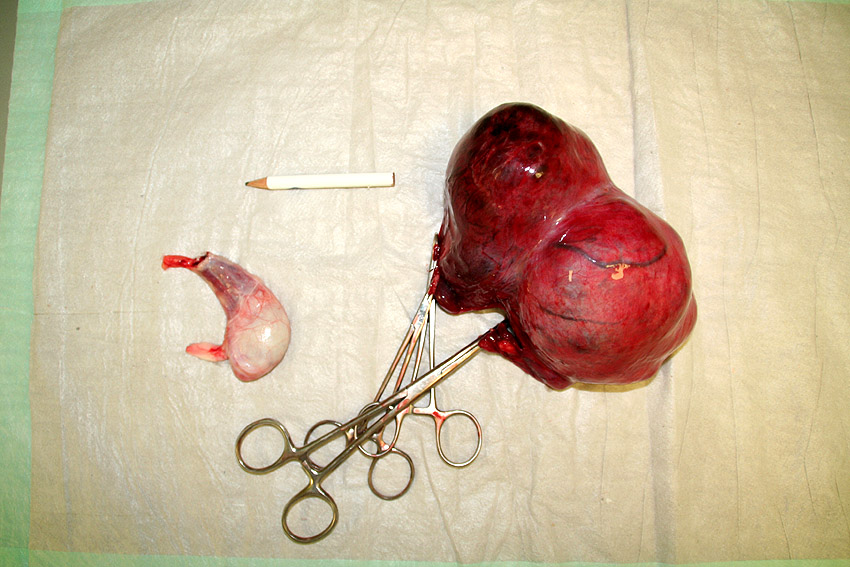

In overleg met de eigenaar hebben we Duco geopereerd. In verband met de tevens vergrote prostaat hebben we de normale testikel ook weggehaald. Daarna is de tumoreuze testikel verwijderd. Hiertoe moesten we een flinke snee maken, het was een grote tumor.

Uiteindelijk is hij er in z’n geheel uitgekomen. Na onderzoek bleek het om een goedaardige tumor te gaan. Dus eind goed al goed!

Hieronder ziet u een aantal foto’s van de operatie:

(bij de verwijderde testikels, ziet u links de normale testikel. Deze is ongeveer 3 cm breed, dit geeft een beeld van de grootte van de tumoreuze testikel).